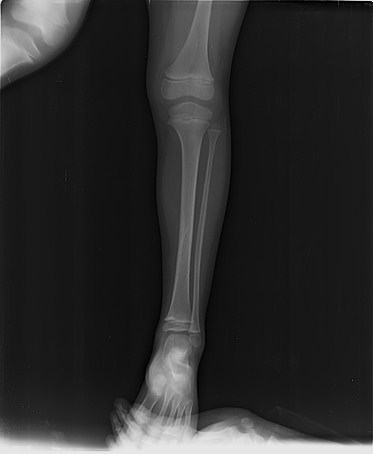

AI-Powered Fracture Detection & Classification

Upload X-ray images via drag-and-drop or select sample images for AI-powered fracture analysis.

Get instant AI diagnosis with confidence scores and medical recommendations in 5-10 seconds.

Review detailed findings and recommendations in the interactive canvas sidebar.

Advanced AI medical imaging tool developed at West Visayas State University for orthopedic fracture detection and classification.

Research-focused X-ray analysis system designed to assist medical professionals in diagnostic imaging.